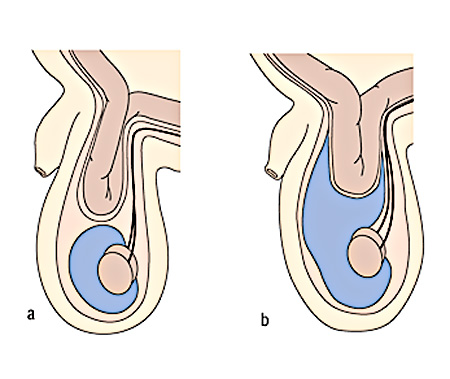

Ábra. és - egy elszigetelt hydrocele és lágyéksérv; b - lágyéksérv, hydrocele szövődményeként.